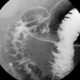

Brunner gland hyperplasia

Brunner's glands (or duodenal glands) are compound tubular submucosal glands found in that portion of the duodenum which is above the hepatopancreatic sphincter (i.e sphincter of Oddi). The main function of these glands is to produce a mucus-rich alkaline secretion i.e. [Source: Wikipedia ]